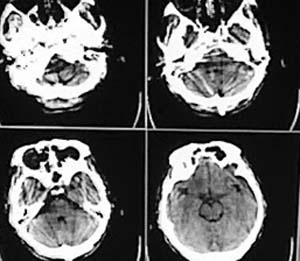

男性,67岁,上楼梯时未扶稳墙后仰摔倒,送入我院,患者诉腰痛头昏,有恶心感。

ct片如下:

枕骨骨折

临床予以止血,降颅内压等处理治疗后5日,患者症状缓解,呕吐恶心症状明显减轻,仍然腰背部疼痛乏力。

复查ct:

支持蛛网膜下腔出血.右额叶脑挫伤

相信各位都会看这种外伤片,发这个帖子的目的在于请大家讨论右侧额、颞叶交界去的低密度到底是脑挫裂伤还是外伤导致周围血管闭塞引起的脑梗塞,请说出理由!!

左额/顶部硬膜下积液,蛛血,右额叶病灶第一次有高密度影,应该是脑挫裂伤,外伤性脑梗塞应该在第一次照片上就出现.

支持蛛网膜下腔出血.右额叶脑挫伤,左额颞部硬膜下积液。

左侧额顶部硬膜下积液,右侧侧裂池内高密度影考虑蛛血,右额叶低密度影是由于脑挫裂伤还是外伤性脑梗塞不好说,但右枕部骨缝,边缘锐利,局部软组织未见异常,不考虑骨折,建议细致观察骨缝边缘有否硬化;考虑枕骨变异可能。